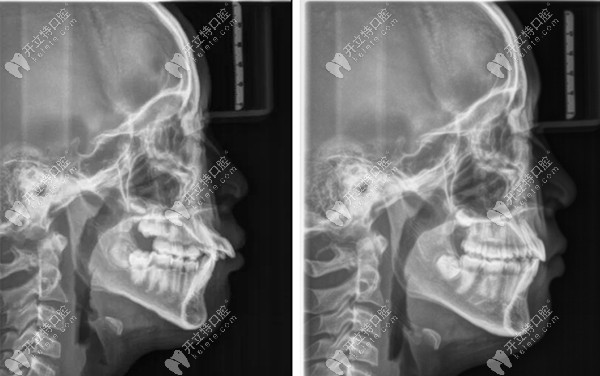

前牙外突治療之后的影響片